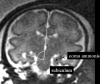

Fig 5.

T2-weighted single-shot, fast spin-echo MR images from the fetal case reported in the “Discussion” section. A and B, Two coronal sections from studies in gestational weeks 23 and 32, respectively, depicting at right temporal-occipital level the abnormal invagination of a cortical sulcus (black arrow). An additional abnormal smaller sulcus is visible (black arrowhead). The normal migrating cells band is focally thinned (white arrowhead). Note the integrity of ventricular wall, excluding the presence of a schizencephalic cleft. C and D, Two axial sections from studies in gestational weeks 21 and 32, respectively, showing the early abnormal cortical sulcus (black arrow), followed later on by the development of multiple abnormal sulci (white arrows).